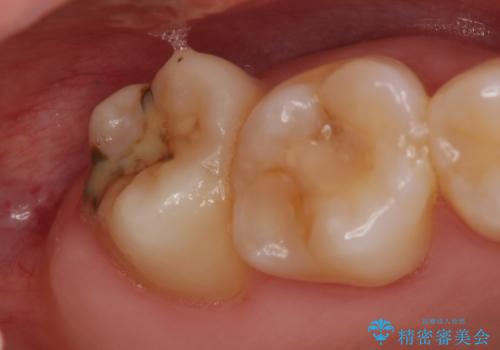

- 冷たいものを飲むと右上の奥歯がしみるので診て欲しいといらっしゃった方の症例です。

右上6番目、7番目の歯の樹脂が劣化していたため、虫歯除去後セラミックインレーによる修復を行いました。